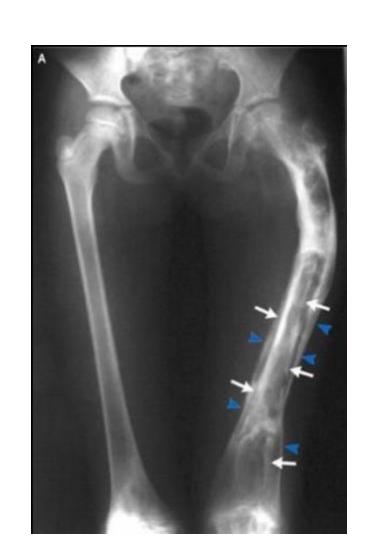

Malignant Bone Tumors

Osteosarcoma

Typical Presentation:

- Age: 10-20 years

- Pain and mass

- Location: Metaphysis of long bone

Characteristic Radiological Findings:

- Sunburst (Sunray) appearance

- Codmanโs triangle

- Periosteal reaction

- Bone eating appearance

Clinical Cases:

-

14-year-old patient with pain and swelling at lower right thigh

- Most important X-ray findings: Sun ray appearance, Codmanโs triangle

- Diagnosis: Osteosarcoma

14-year-old patient complaining of pain and swelling at lower R thigh

- Findings: Codmanโs triangle, Sun burst appearance

Ewing Sarcoma

Clinical Features:

- Occurs in children

- Throbbing pain

- Can be confused with chronic osteomyelitis

- Poor prognosis

11-year-old presented with symptoms - diagnosis on imaging

- Diagnosis: Ewing sarcoma

Case scenario provided with picture